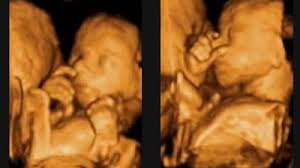

Ich habe gelesen das das kleine die tieferen Töne anfangs besser wahrnehmen kann als die hohen deshalb soll der Papa auch viel mit dem kleinen im Bauch reden. Es kann dann den Herzschlag und die anderen Geräusche im Bauch der Mutter hören sowie auf akustische Reize von aussen reagieren.

Blau und Lila dauern etwas länger da diese Farben kürzere Wellenlängen haben und das menschliche Auge weniger Rezeptoren für Blautöne besitzt. Es kann dann den Herzschlag und die anderen Geräusche im Bauch der Mutter hören sowie auf akustische Reize von aussen reagieren. Unsere kleinen hören ab der 14. Bis Du Dir sicher dass bei den Angaben 56. Dein Baby kann bereits hören bevor es überhaupt das Licht der Welt erblickt. Schwangerschaftswochen hören können - und darauf reagieren. Meine frage daher lautet ab welche SSW hört man die Herztöne vom Baby. SSW mit dem Stethoskop hören können. Es nimmt zum Beispiel Deinen Herzschlag und das Rauschen Deines Blutes wahr und selbst Stimmen von außen dringen zu ihm vor.